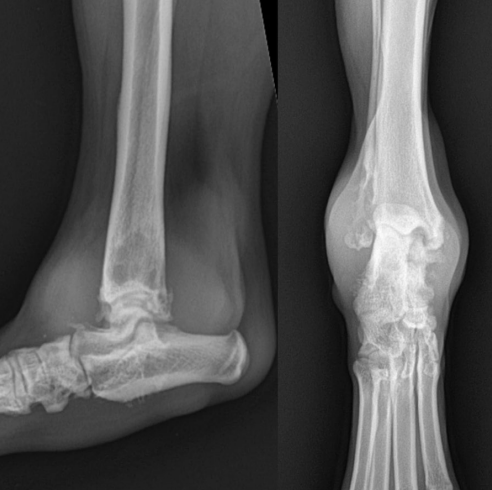

- ๊ด์ ์์ธก์์ ๋ผ์ ๋ณํ๊ฐ ๋ํ๋จ - subchondral bone & cortex์ lysis, new bone production

![]() | - lining์ ๋ณํ - ์ค๋ฅธ์ชฝ์ ๋ผ๊ฐ ๋ค ๋ น์ ์ ๋จํ ์๋ฐ์.. |